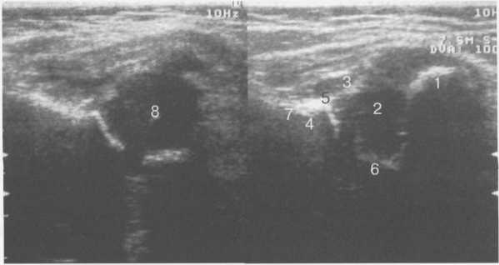

При сканировании из переднего доступа оценивают тазобедренный сустав и мягкие ткани паховой области, мышцы. Исследование сустава проходит продольным сканированием вдоль оси шейки бедра. Получают изображение переднего края крыши вертлужной впадины, вертлужной губы (хрящевого лимбуса, labrum acetabulare), которая дифференцируется как треугольная гиперэхогенная структура, а также передней поверхности головки бедренной кости, являющихся костными ориентирами. Отчетливо прослеживается тонкий суставной гипоэхогенный гиалиновый хрящ головки бедра (рис. 19.81). Собственно суставная капсула визуализируется вместе с волокнами преимущественно подвздошно-бедренной связки (рис. 19.82). Для определения отсутствия или наличия выпота в суставе измеряют расстояние между передней поверхностью шейки бедра и гиперэхогенной капсулой.

Рис. 19.81. УЗИ тазобедренных суставов взрослого.

1 — головка бедренной кости; 2 — шейка бедренной кости; 3 — капсула сустава и lig. iliofemorale; 4 — хрящевой (фиброзный) лимбус.

Рис. 19.82. УЗИ тазобедренного сустава по передней поверхности вдоль шейки бедра (8 лет).

1 — головка бедренной кости; 2 — шейка бедренной кости; 3 — капсула сустава и lig. iliofemorale; 4 — хрящевой (фиброзный) лимбус; 5 — зона роста.